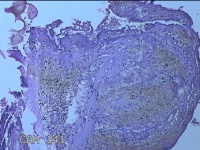

子宫腔妊娠残留物

早期人工流产术后 疤痕子宫 不全流产?

停经11周。

灰白暗红色不规则碎组织4x3.5x0.8cm一堆,未发现明显的绒毛样组织。